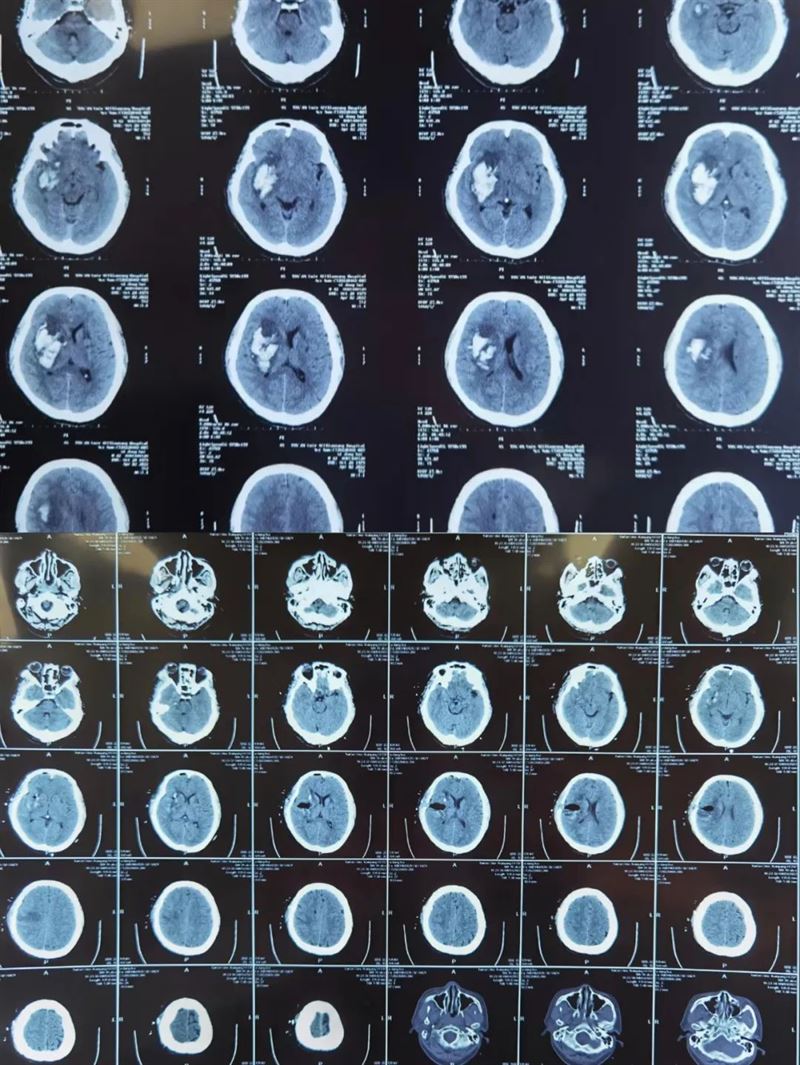

之前,我院急診科緊急接來了一名陷入深昏迷狀態(tài)的男性病人,患者入院后急查頭顱CT提示顱內出血,量約90ml。亓乾偉副主任醫(yī)師接治病人后,發(fā)現患者雙側瞳孔不等大,一側瞳孔已經散大,病情危急,充分告知患者家屬當前病情及預后情況,顱內出血量大,發(fā)病時間短,隨時存在呼吸心跳驟停可能,危及生命,建議緊急手術治療,與其妻子及遠在北京的女兒電話聯(lián)系并取得家屬同意后,在入院1小時內緊急行開顱手術,術中清除血腫并仔細止血后,在其腦表面發(fā)現腫瘤病灶,一并切除病灶并送病理檢查。術后患者生命體征平穩(wěn),復查頭顱CT可見血腫清除滿意,將患者從死神手中拉回。術后病理結果提示肝細胞轉移瘤,并予以相應治療。患者妻子及女兒拉著他的手說到:“要不是您,我都沒有機會再見我父親最后一面,將會徹底失去我盡孝的機會。”

此類事跡數不勝舉,就在5個月前的一個凌晨,神經外科一病區(qū)接診了一名男性腦外傷患者,據陪同來的房東所述,患者是藏族人,21歲,孤身一人來到咸陽,其余信息都無從所知,當時患者病情十分危急,意識呈昏迷狀態(tài),瞳孔散大,去腦強直,呼吸微弱,如不進行緊急搶救,年輕的生命將離我們而去。科室劉增強主任立即啟動急救綠色通道,亓乾偉醫(yī)生徹夜未眠,歷經5個多小時的艱苦奮戰(zhàn),手術順利完成,但患者仍然未脫離危險,呼吸機維持呼吸,在亓乾偉醫(yī)生的精心治療下,終于在術后1周患者自主呼吸恢復,術后1月患者意識恢復,術后2月患者已完全康復,下地活動自如,順利出院。患者父母以藏族特有的方式為亓乾偉醫(yī)師獻上了潔白的哈達,送上了藏族特有的祝福“扎西德勒”。

(術前術后對比)